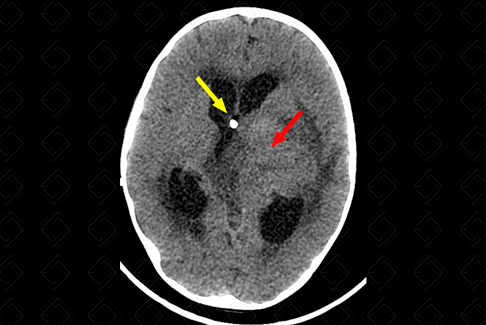

Texto alternativo para a imagem Figura 2. Créditos: Dra. Elazir Mota - Rio de Janeiro/RJ

Descrição da figura 6: Tomografia computadorizada do crânio, plano axial evidenciando ventrículos laterais dilatados, por lesão expansiva que comprime o ventrículo lateral esquerdo e o forame de Monro (seta vermelha). Há ainda transudação liquórica pela hidrocefalia e observa-se ponta do cateter de derivação ventriculoperitoneal (seta amarela). [cms-watermark]